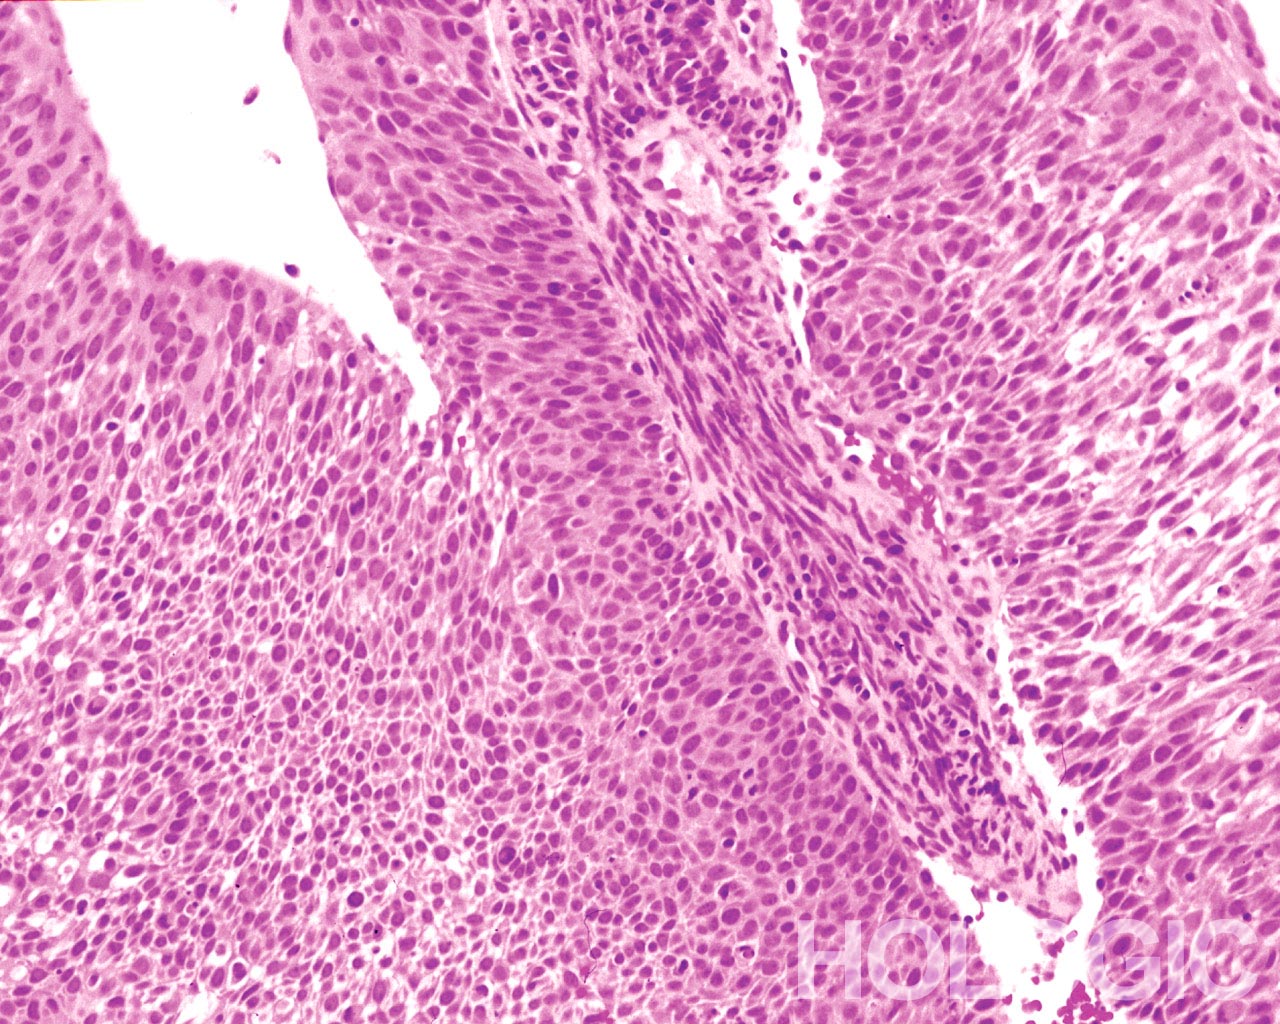

Plaveiselcelcarcinoom (SCC) is het meest voorkomde maligne neoplasma van de baarmoederhals. Hoewel sub-classificatie niet is vereist in het Bethesda Systeem, is het gebruikelijk om deze tumoren klinisch onder te verdelen in niet-keratiniserende en keratiniserende vormen.

Dit is de meest voorkomende vorm van carcinoom in de cervix. Deze cellen zijn meestal middelgroot tot groot en komen overwegend in groepen of syncytia voor. Het cytoplasma van niet-keratiniserende plaveiselcelcarcinoom kleurt gewoonlijk cyanofiel en zal er dens en licht gevacuoliseerd uitzien. Deze vacuolisatie van het cytoplasma kan er voor zorgen dat de cytoloog de diagnose van glandulaire laesie overweegt, maar de celcriteria moeten aanleiding geven een squameuze categorie te selecteren. De groepen van niet-keratiniserende SCC komen voor in een “plattere” laag met minder duidelijke cytoplasmische groepsgrenzen dan adenocarcinoom en missen de echte glandulaire kenmerken, zoals rozetten/aciniformaties, geschulpte grenzen, columnaire dfferentiatie of elongatie en op elkaar gepakte kernen.

De kernen zijn vergroot met een kern/cytoplasma-ratio die eerder matige dysplasie dan naar een CIS. De klassieke maligne kerneigenschappen geven aan dat dit eerder een carcinoom dan een plaveiselcel intraepitheliale laesie is. Het chromatinepatroon is vrij wisselend, meestal grofkorrelig en onregelmatig verdeeld met prominente lege plakken in het parachromatine. De nucleaire kernmembraan is zeer onregelmatig en zeer onregelmatig gevormde nucleoli zijn gebruikelijk. Deze kenmerken bepalen de diagnose van maligniteit voor deze entiteit.